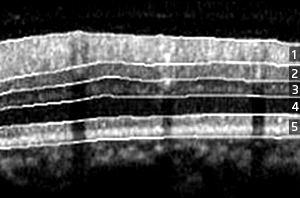

Fig. 1: Automatic segmentation of a spectral-domain OCT retinal image into five layers. The glaucoma can be diagnosed based on the thickness variation of the nerve fiber layer. 1, retinal nerve fiber layer; 2, ganglion cell layer; 3, inner plexiform/nuclear layer; 4, outer plexiform/nuclear layer; 5, photoreceptor layer.

Lu and his co-workers developed a system that automatically segments images generated by spectral-domain OCT into five retinal layers, including the RNFL (Fig. 1). “Our system is specifically designed for computer-aided diagnosis of glaucoma and other eye diseases, and has features not found in previously proposed methods for analyzing OCT images,” says Lu.